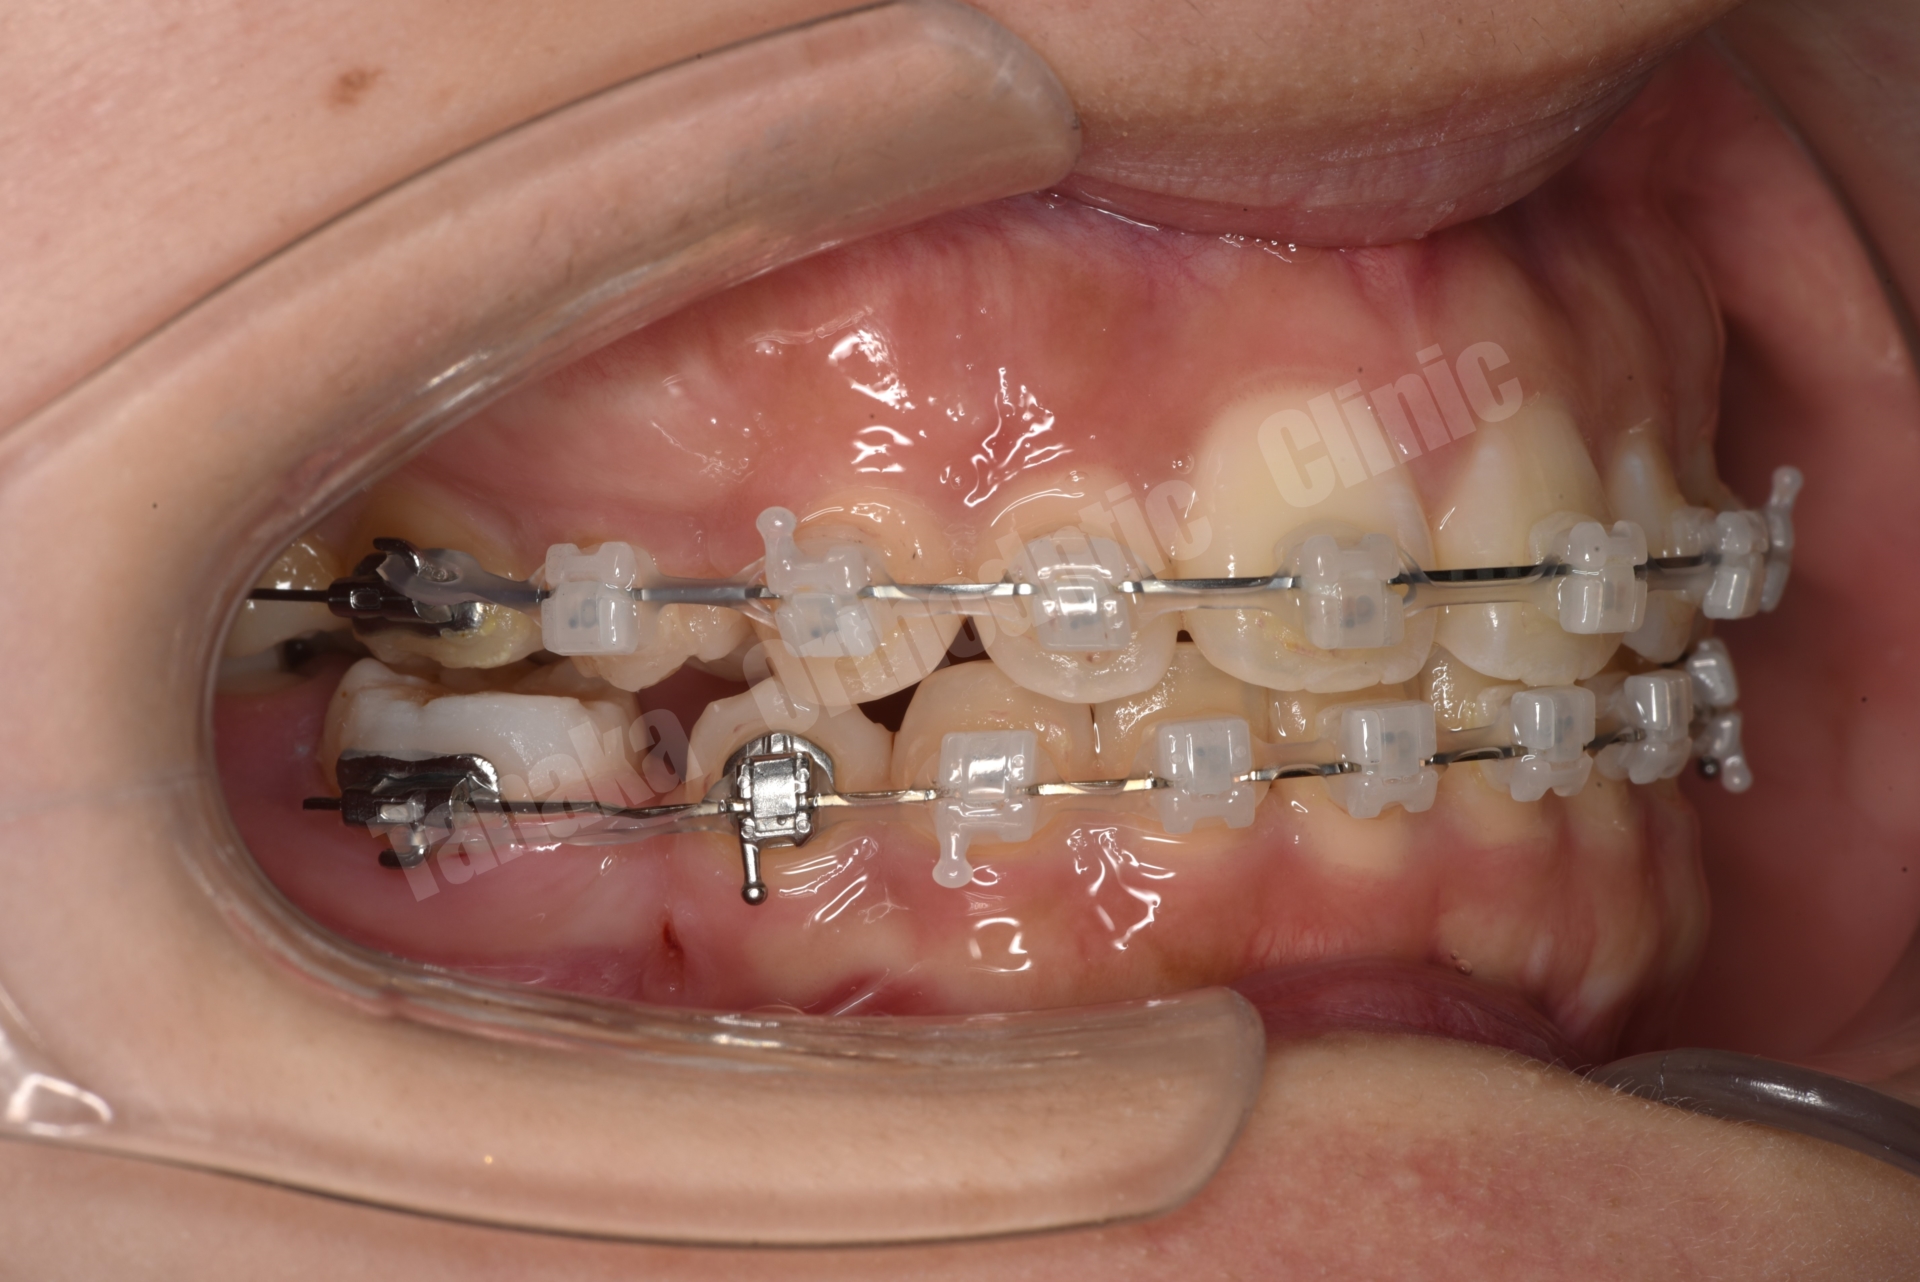

そこで治療では上下歯列に唇側マルチブラケット装置を装着し、歯列全体の排列を行いました。上顎前突を改善するため上顎両側4番を抜歯し、前歯を後退させて口元のバランスを整える計画としました。さらに下顎正中の改善のため右下Eを抜歯し、約11mmある乳臼歯部のスペース閉鎖を行う計画としました。このスペース閉鎖には矯正用アンカースクリューを使用し、右側6番・7番を近心移動させる必要があります。また治療途中で萌出してくる右下7番の位置を適切にコントロールすることも重要なポイントとなります。

今回の症例では、11mmという比較的大きなスペース閉鎖に加え、治療途中で萌出してくる7番のコントロールも必要となるため、通常より難易度の高い治療となりました。そのため治療期間は通常よりやや長くなる可能性を考慮し、2年以内での治療終了を目標として治療を開始しました。